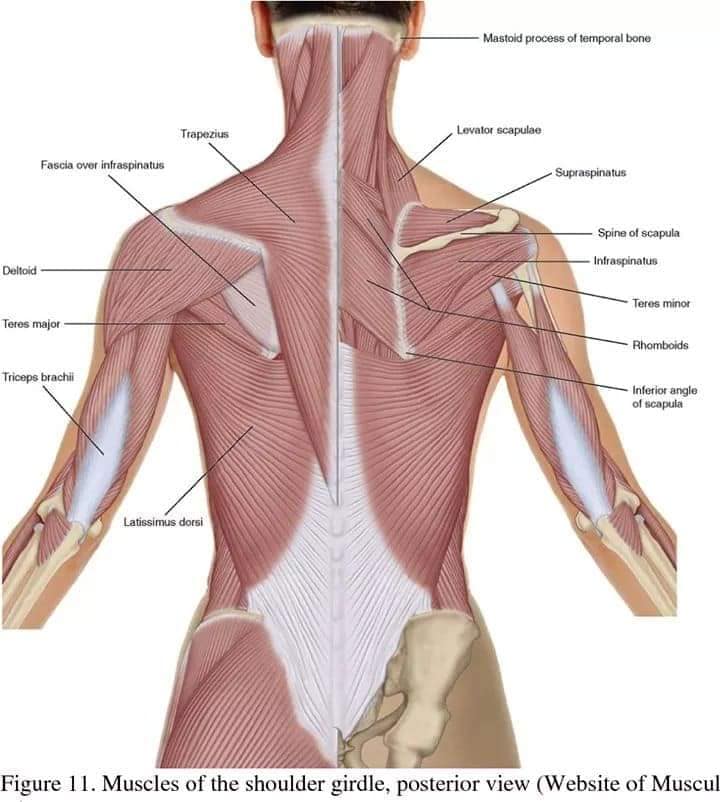

М'язи, що розширюють шию: М'язи, що розширюють шию: включають трапецієподібний м'яз, який бере участь у піднятті плечей і розширенні шиї.

Спинні м'язи виконують функції підтримки хребта, а також дозволяють здійснювати рухи тулуба.

Поверхневі спинні м'язи

М'язи, що піднімають лопатку: Трапецієподібний м'яз: великий м'яз, що покриває верхню частину спини. Його функція - підтримка і рух лопаток, а також забезпечення стабільності хребта.

М'язи, що ведуть лопатку до хребта: Широкий м'яз спини: великий м'яз, що розташований в нижній частині спини. Він відповідає за рухи плечей і лопаток, а також за розширення верхньої частини тулуба.

Глибинні спинні м'язи

М'язи, що забезпечують стабільність хребта: М'язи, що розташовані між хребцями: включають мускулатуру, яка забезпечує стабільність і підтримку хребта, а також дозволяє здійснювати рухи хребта.

М'язи, що здійснюють ротацію та нахили

М'язи, що забезпечують ротацію хребта: Ротаційні м'язи: допомагають у здійсненні обертальних рухів тулуба, а також у підтримці рівноваги і стабільності хребта.

Важливість шийних і спинних м'язів

Шийні і спинні м'язи грають критичну роль у підтримці правильної постави, регуляції рухів голови і тулуба, а також у запобіганні травмам і болю.